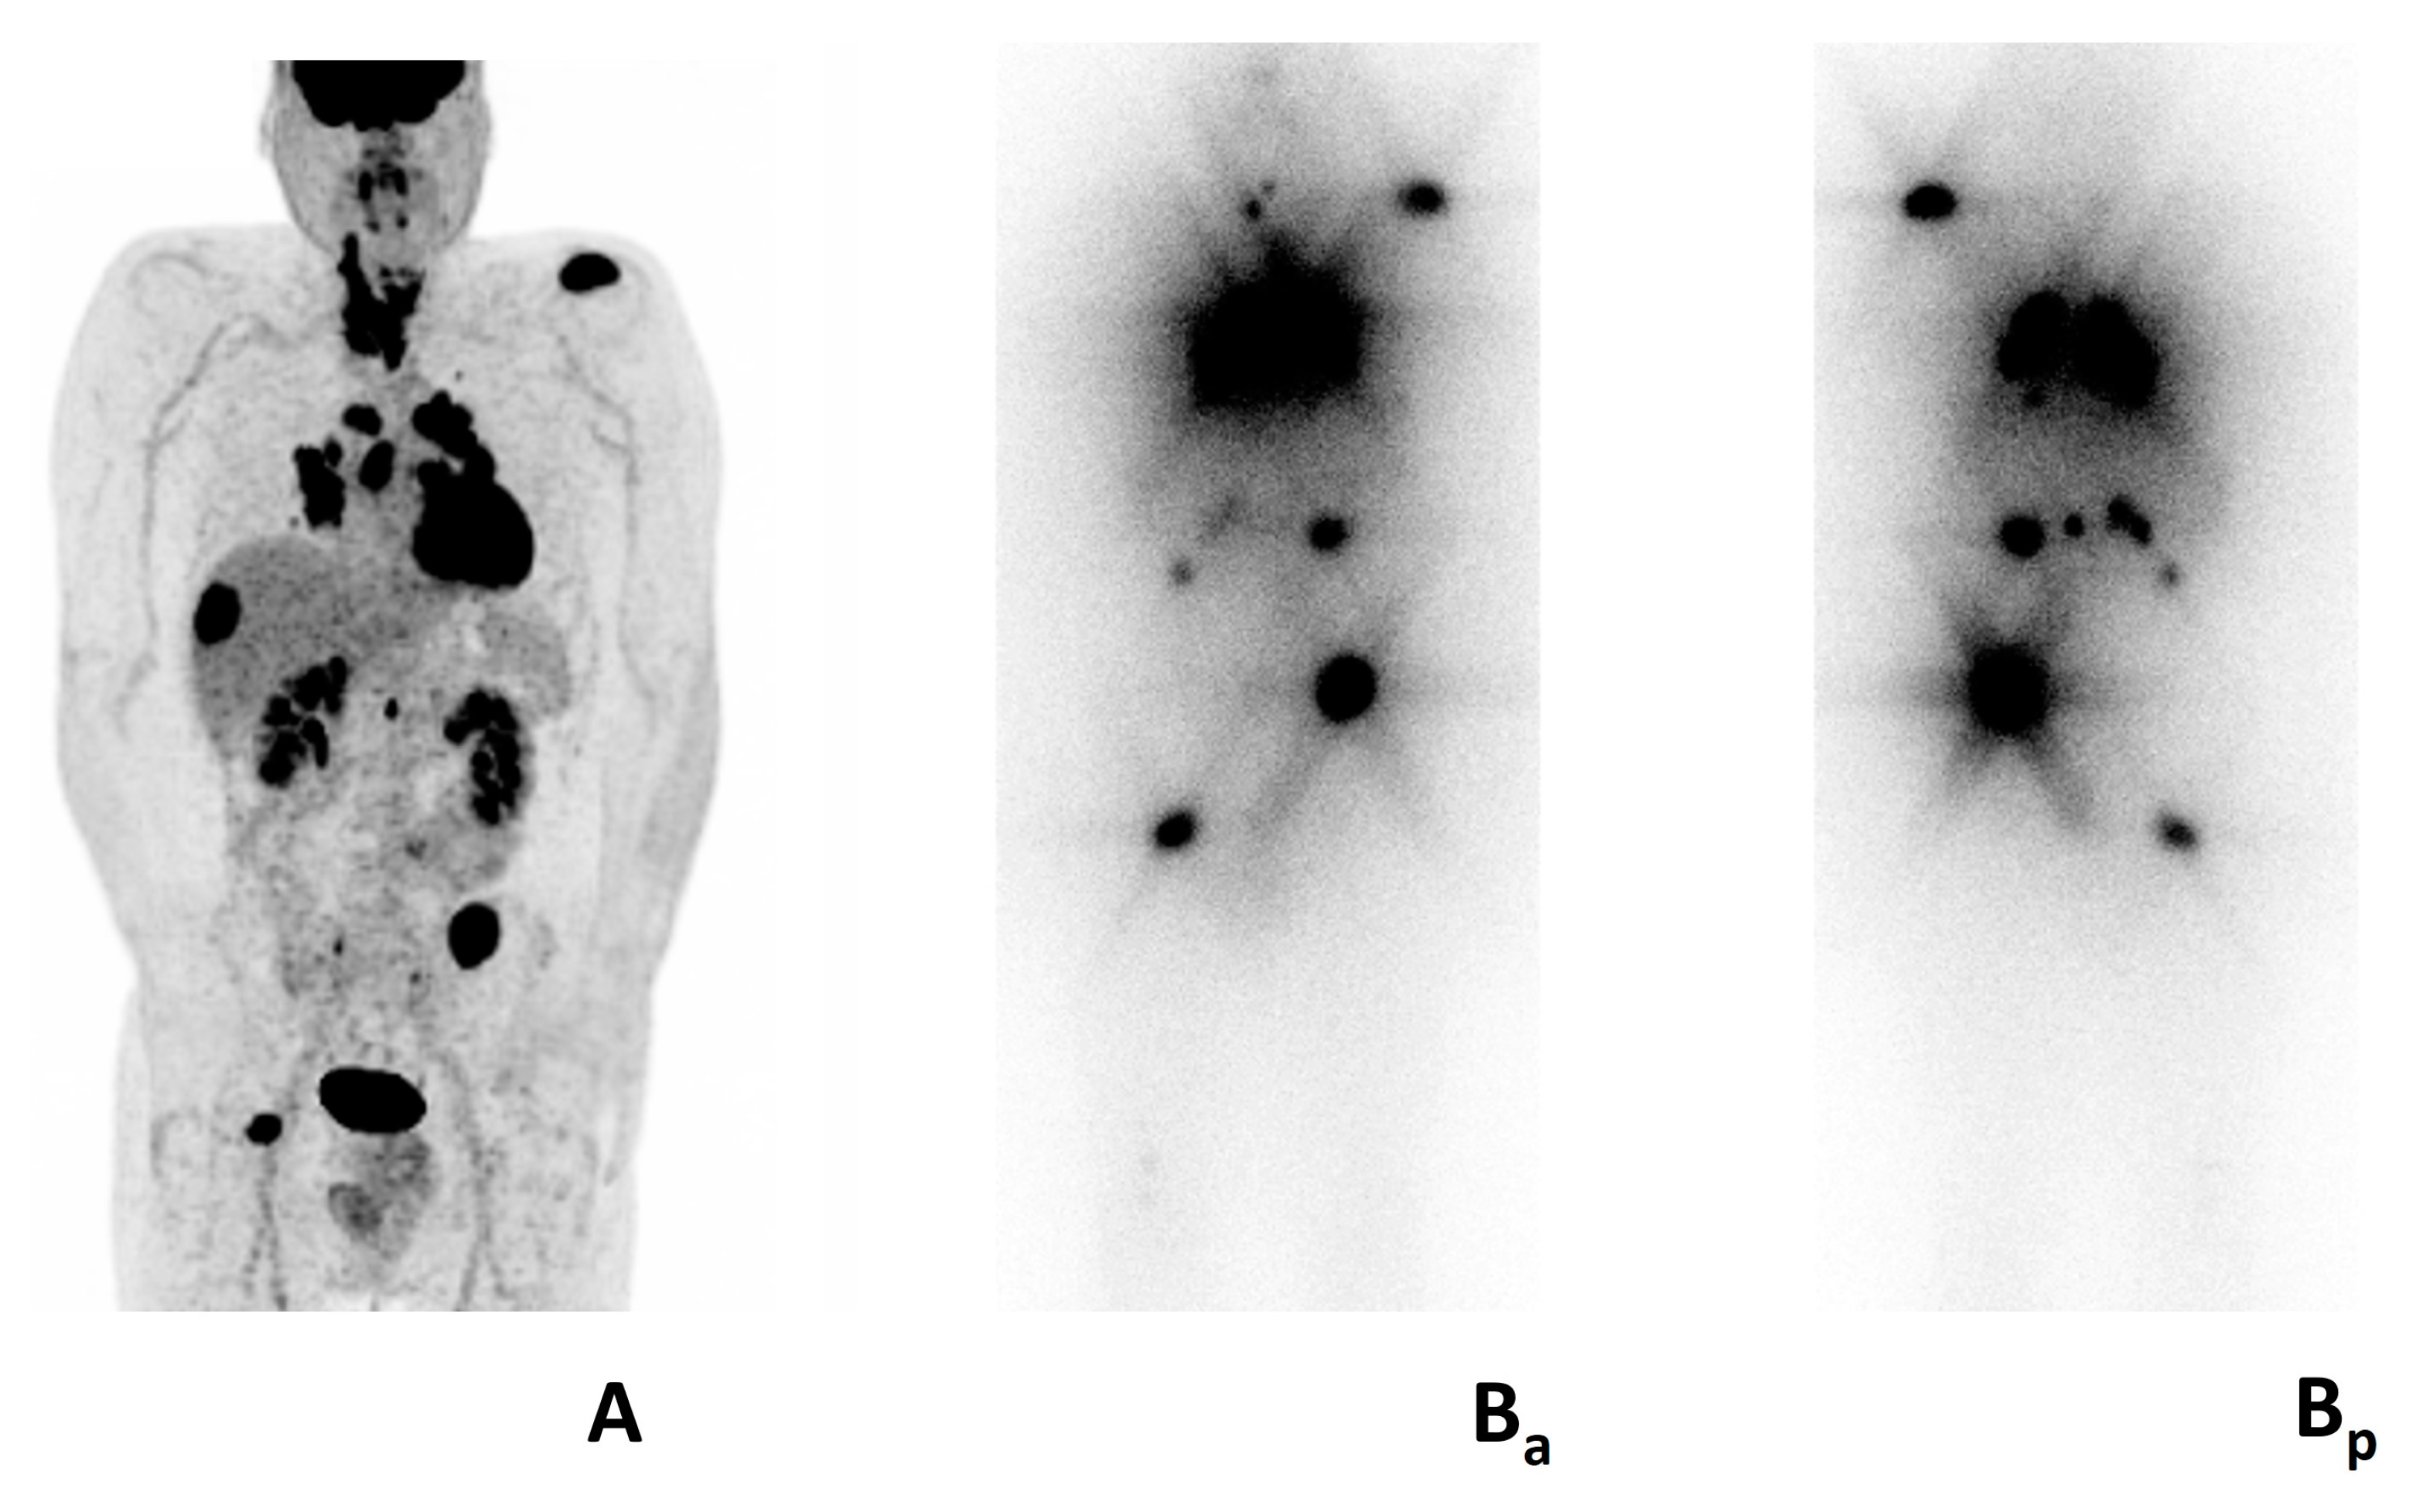

- Iravani, A.; Solomon, B.; Pattison, D.A.; Jackson, P.; Ravi Kumar, A.; Kong, G.; Hofman, M.S.; Akhurst, T.; Hicks, R.J. Mitogen-Activated Protein Kinase Pathway Inhibition for Redifferentiation of Radioiodine Refractory Differentiated Thyroid Cancer: An Evolving Protocol. Thyroid 2019, 29, 1634–1645. [Google Scholar] [CrossRef]